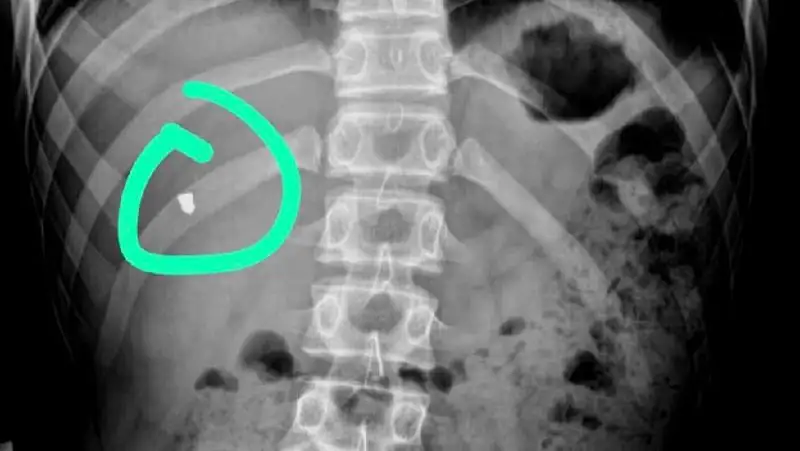

В Мангистау из грудной клетки 16-летнего подростка вытащили пулю от пневматического оружия, передает Zakon.kz.

Он сообщил, что 19 февраля в приемный покой областной детской больницы Мангистау был доставлен 16-летний подросток с пулевым ранением в грудную клетку. По словам сопровождающих, подросток по неосторожности получил ранение в одном из аттракционов (тир), находящемся в парке «Акбота».

После полного обследования 22 февраля врачи детской больницы провели сложнейшую операцию по извлечению инородного предмета из грудной клетки подростка.Азамат Сарсенбаев

По словам врачей, операция длилась примерно 40 минут.

Благодаря современному оборудованию эндоскопии в стенах детской больницы им (врачам. - Прим. ред.) удалось провести сложную операцию без существенных проблем. В противном случае, сетуют врачи, им бы пришлось вскрывать грудную клетку для того, чтобы вытащить инородное тело. В настоящий момент подросток чувствует себя хорошо и готовится к выписке.Азамат Сарсенбаев